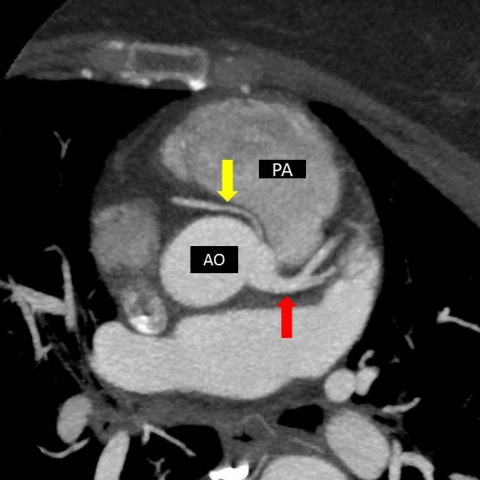

Axial MIP image shows common origin of RCA and left main coronary artery from left aortic sinus. Anomalous inter-arterial course of RCA between aorta (AO) and pulmonary artery (PA).

This interarterial course can lead to compression of the LCA (yellow arrows) resulting in myocardial ischemia.